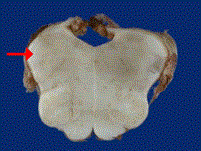

问题 如图箭头所示为小脑哪个部位 ( )

选项 A、小脑上脚 B、小脑蚓部 C、小脑下脚 D、小脑扁桃体 E、小脑中脚

答案 C